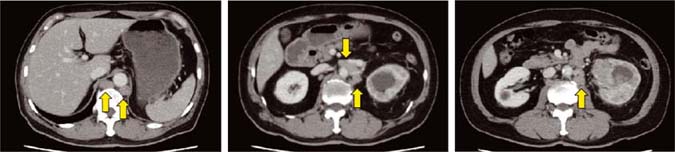

A 65-year-old Japanese male diagnosed with left renal pelvic cancer was referred to us. He had visited another hospital due to gross hematuria. Incidentally, his daughter had undergone nephrectomy for kidney cancer at the age of 36 years. Physical examinations, including the skin, revealed no abnormal findings. Laboratory findings showed hematuria, elevated serum creatinine (1.47 mg/dL), and C-reactive protein (12.1 mg/L). Urine cytology showed atypical urothelial cells. Computed tomography (CT) scans identified a moderately enhanced mass occupying the left renal pelvis, in addition to hydronephrosis, multiple para-aortic lymphadenopathy, and left adrenal swelling (Figure 1).

Figure 1: Computed tomography at the first visit. A moderately enhanced mass occupies the left renal pelvis, accompanying hydronephrosis and multiple para-aortic lymphadenopathy (arrows).